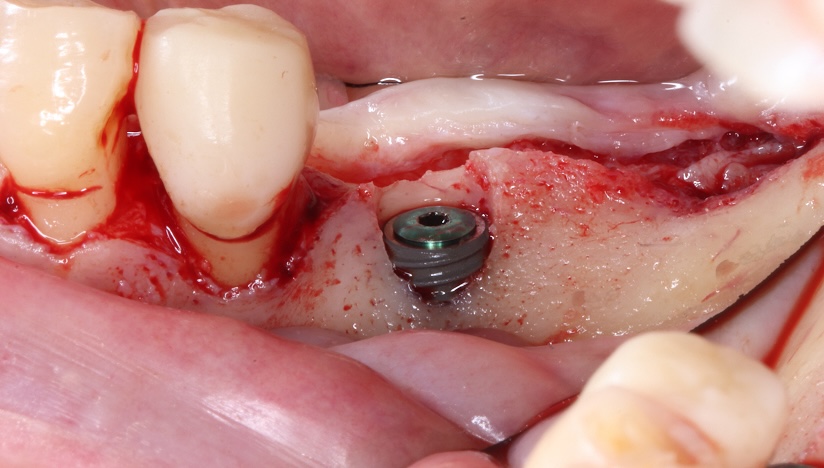

骨造成により

理想的な骨幅を回復させた

インプラント症例

タップで写真の拡大ができます。

主訴

右下奥歯で噛むと痛みがある

診断

歯周病による歯槽骨吸収および垂直性歯根破折

治療方針

遊離端欠損となるため、入れ歯またはインプラントが選択肢となる症例。 硬いものをしっかり噛みたいという希望があり、インプラントを選択した。

また、水平的な骨吸収が認められたため、 インプラント埋入と同時にGBRを併用する方針とした。

治療内容

抜歯即時インプラント埋入およびGBR

治療期間

約6〜8ヶ月(骨造成を伴うため)

治療費用

1,500,000

結果

水平的に十分な骨幅が獲得され、インプラントの安定も良好に得られている。

治療の

リスク

創部の早期裂開が生じた場合、移植材の除去および再手術が必要となる可能性、下顎神経麻痺、出血・血腫

考察

骨量が不足する症例においては、GBRを先行して行う方法も選択肢となる。

本症例では抜歯窩からの血液供給も利用し、インプラント埋入と同時にGBRを行うことで、良好な骨造成と治癒が得られた。

その結果、治療期間の短縮と外科的侵襲の低減が可能となった。